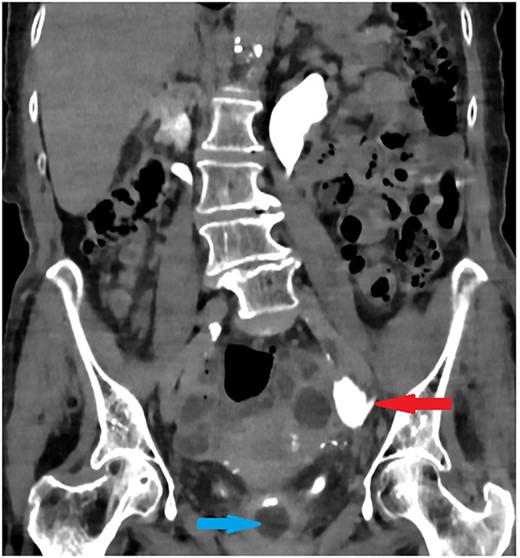

On examination, the patient was feverish (temp 38.2) and had left sided abdominal pain without tenderness on palpation. Her blood investigations did not show any significant changes. Initial washout through the catheter increased the pain and it showed passive drainage only. Non-contrast computed tomography (CT) was performed to assess the catheter position. Surprisingly, the catheter was passing into the left ureter with the catheter balloon inflated in the mid-ureter (Fig. 1).

Coronal section of abdomen and pelvis non-contrast CT: The urethral catheter migrates into the left ureter up to the mid-ureter.